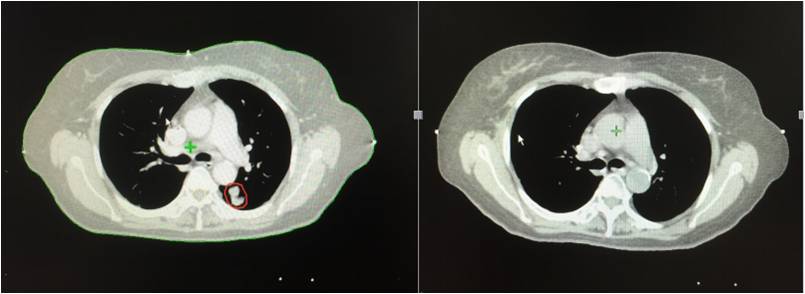

治疗前 治疗后

患者因出现上腹痛伴厌食、消瘦3月余,加重半月就诊,2016年2月CT显示为胰腺头部占位性病变,进一步检查确诊为胰头癌(cT4N0MO,III期),肿瘤标志物:CA19-9 1227.8 U/ml,CEA 18.52 ng/mL。患者疼痛明显,口服止痛药(可待因及曲马多片q8h)缓解较差,且伴有纳差,无法手术及化疗。2016年4月,患者慕名前往全球肿瘤医生网寻求帮助,经过全球肿瘤医生网专家评估,推荐患者接受安全无创的A45综合治疗。

治疗后增强CT显示:胰头肿块,约4cm,中央坏死,增强扫描无强化(2016-06-21)

复查肿瘤标志物均降低。

患者接受A45治疗半个疗程疼痛明显缓解,止痛药由q8h改至q12h且改为一种,治疗后程患者止痛药剂量及口服频次进一步减少(改为qd),且疼痛基本缓解,治疗结束后3-5天疼痛消失,停用止痛药,且进食较前明显增加。